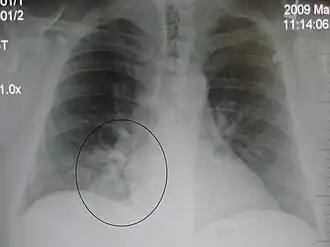

A black and white X-ray picture showing a triangle white area on the left side. A circle highlights the area.

A chest X-ray showing a very prominent wedge-shape bacterial pneumonia in the right lung

The discovery of x-rays made it possible to determine the anatomic type of pneumonia without direct examination of the lungs at autopsy and led to the development of a radiological classification. Early investigators distinguished between typical lobar pneumonia and atypical (e.g. Chlamydophila) or viral pneumonia using the location, distribution, and appearance of the opacities they saw on chest x-rays. Certain x-ray findings can be used to help predict the course of illness, although it is not possible to clearly determine the microbiologic cause of a pneumonia with x-rays alone.